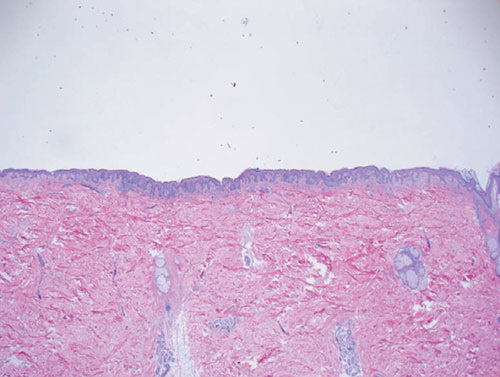

Atypical compound (dysplastic) nevus =وحمة مركبة عسيرة التصنع غيرنموذجية